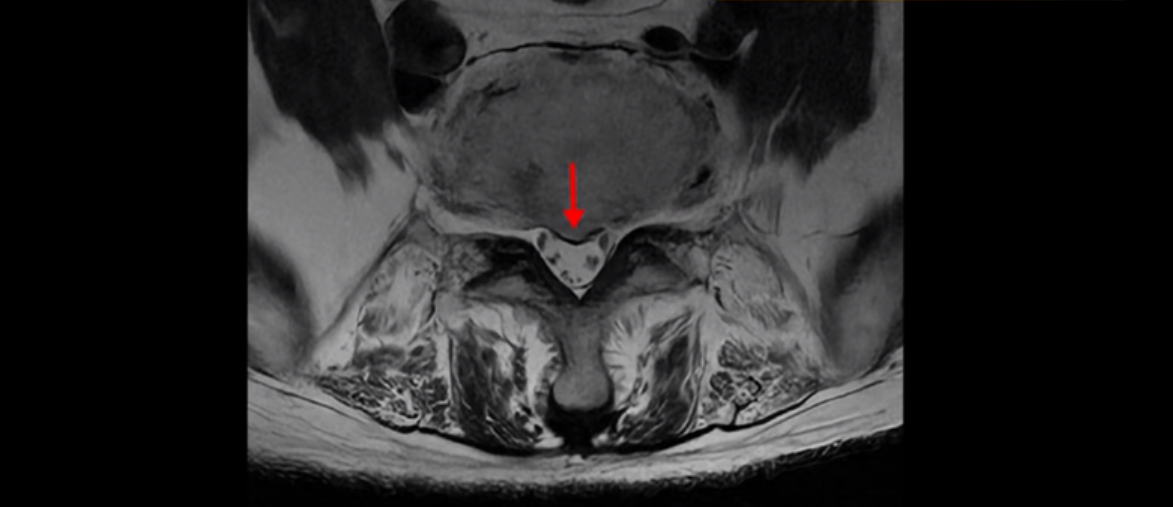

4번 5번에는 척추관협착과 심한 디스크 파열이 있습니다.

5번 1번에는 뼈가 자라난 골극이 있고

기립근의 지방화도 심합니다. 또 3번 4번 마디에서는 신경가지가 빠져나가는 추간공이 왼쪽, 오른쪽 모두 많이 좁아져 있습니다.

이런 이유로 이 환자분은 왼쪽 다리는 마비가 생겨 힘이 빠지고 오른쪽 다리에는 심한 방사통이 있어서 휠체어까지 타야 하는 상태가 되었습니다. 이렇게 심하니까 대학병원에서 여러 마디 나사를 박는 유합술을 권유 받으셨는데요.